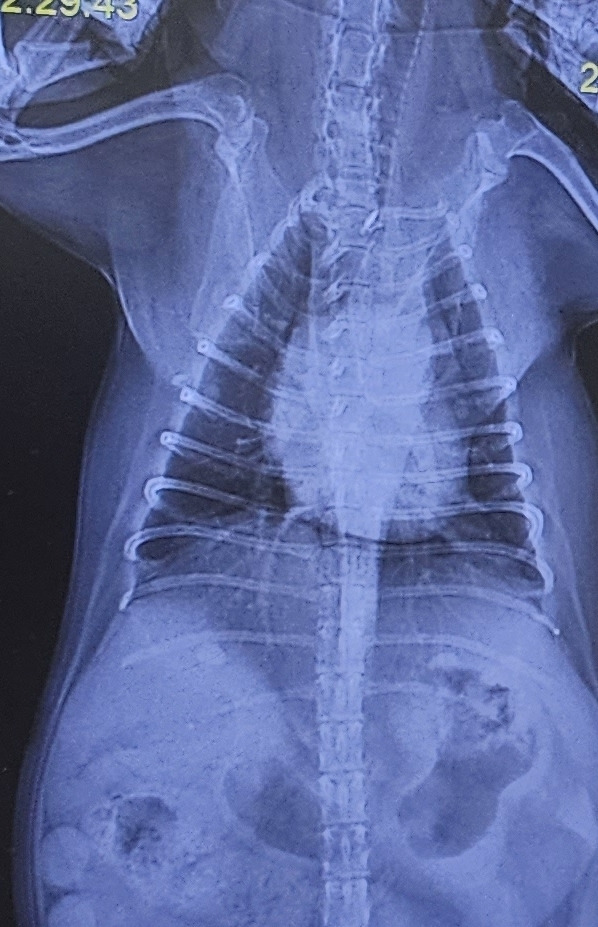

엑스레이 사진(왼쪽)을 보면 물이 많이 차서 심장과 폐를 구분할 수가 없다.

왼쪽 5월 5일 새벽. 오른쪽 5월 5일 오후